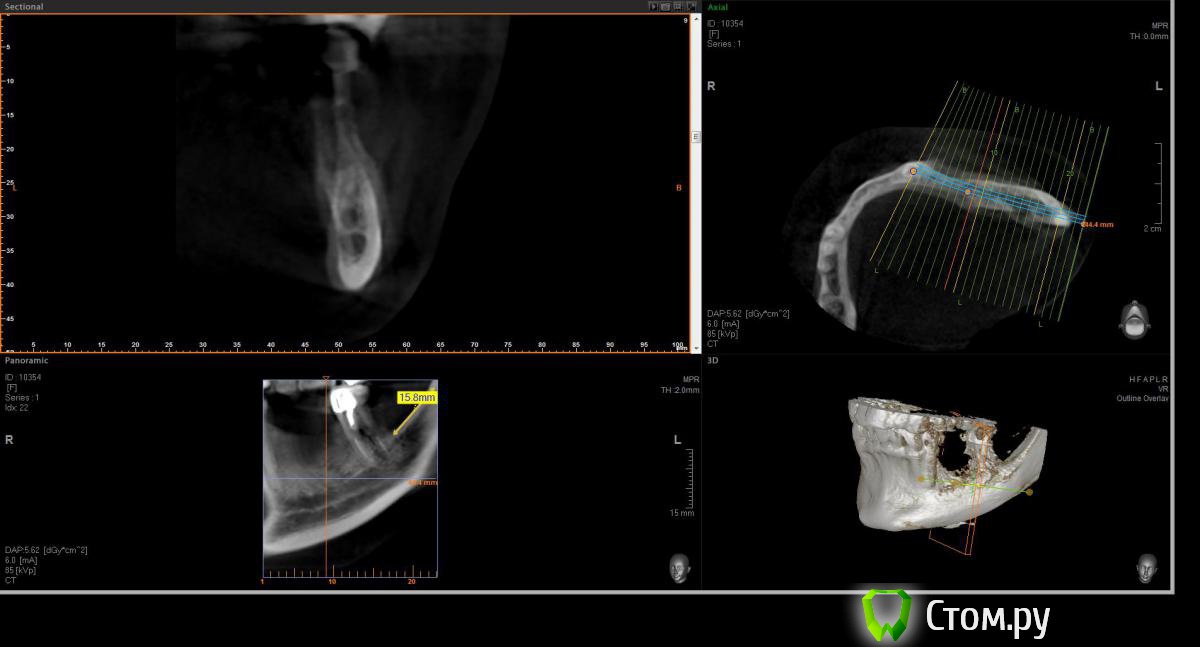

Opimar Опубликовано 21 июня, 2014 Поделиться Опубликовано 21 июня, 2014 Здравствуйте коллеги. Прошу вашей помощи и совета с пациенктой. В анамнезе травматичное удаление около 2-3 лет назад 35-36. Со слов пацинтки удалялось долотом и в 2 приема, вообщем по прошествию времени результат плачевный К мостовидному протезу пациентка не готова, очень хочет лечение с имплантантами и готова к костной пластике. Восстановить такой дефект ,если я правильно понимаю, более-менее прогнозируемо можно только с трансплантацией аутокостных блоков. Как раз по типу того как выкладывал Mane http://forum.stom.ru/topic/25799-kk-monokortikalnye-bloki/ либо по Кюри. Сам склоняюсь к забору блока с наружной косой линии или с подбородка. С блоками работать буду первый раз. Прослушал курсы Томаса Хансера. Прошу высазать идеи и предложения,возможны ли альтернативные методы? Кт прилагаю. Спасибо Ссылка на комментарий

Opimar Опубликовано 21 июня, 2014 Автор Поделиться Опубликовано 21 июня, 2014 Выкладываю еще. Пошагово от 34-37 Ссылка на комментарий

Bier Опубликовано 21 июня, 2014 Поделиться Опубликовано 21 июня, 2014 Выкладываю еще. Пошагово от 34-37темная точка достаточно высоко, это по моему не нерв, нерв ниже, я правильно понимаю? Ссылка на комментарий

Opimar Опубликовано 21 июня, 2014 Автор Поделиться Опубликовано 21 июня, 2014 темная точка достаточно высоко, это по моему не нерв, нерв ниже, я правильно понимаю?Да он ниже и язычнее. Провел от менталиса там еще запас есть. Ссылка на комментарий